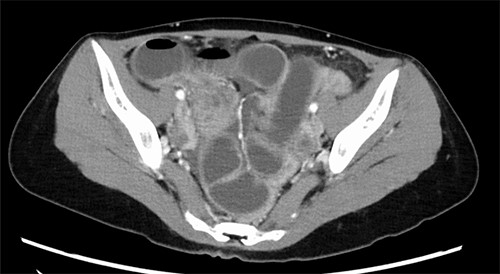

A 37-year-old woman presented with an acute onset of diffuse abdominal pain and vomiting unrelated to menstruation. The patient had no history of abdominal surgery, including a caesarean section. Her faecal occult blood test results were positive for the last 3 years, and the annual colonoscopy did not reveal any abnormalities. She had ileus of unknown cause and had undergone conservative medical management at another hospital 1 year prior. Physical examination revealed abdominal distention and peritoneal irritation. Blood examination revealed a slightly elevated circulating white blood cell count of 10 020/μl, but other laboratory data were within the normal range. Computed tomography (CT) revealed ascites and a small bowel obstruction at the level of the distal ileum (Fig. 1). Her abdominal symptoms worsened quickly during the period in which these tests were performed, and she presented with panperitonitis. Therefore, immediate surgical intervention was planned. Intraoperatively, a stricture in the distal ileum, ~5-cm oral from the Bauchin valve, was observed with haemorrhagic ascites. A mass lesion was observed at the tip of the appendix, infiltrating the terminal ileum (Fig. 2). Abnormal findings, such as twitching or pigmentation, were not observed in the serosa at the same site. We performed ileocecal resection with lymph node dissection during complete mesocolic excision, considering a malignant tumour of the intestine. Macroscopically, the resected specimen showed swelling of the appendix, thickening of the intestinal wall and stenosis of the ileum (Fig. 3A and B). Histopathological examination showed fibrous wall thickening and luminal stenosis/obstruction of the appendix by marked fibrosis. Ectopic endometrial glands and stroma were scattered in the thickened appendiceal wall. Fibrous adhesion of the ileum with the appendix was seen, and ectopic endometrial tissues were also scattered in the subserosa and muscularis propria of the ileum at the adhesion site (Fig. 4A–C). These findings were compatible with appendiceal and ileal endometriosis. Sampled lymph nodes did not show findings of endometriosis. The patient was discharged on post-operative day 12 and had an uneventful course without postsurgical hormonal therapy or recurrence of endometriosis.

Abdomino-pelvic CT image; dilatation of the small bowel with transition point at the terminal ileum.